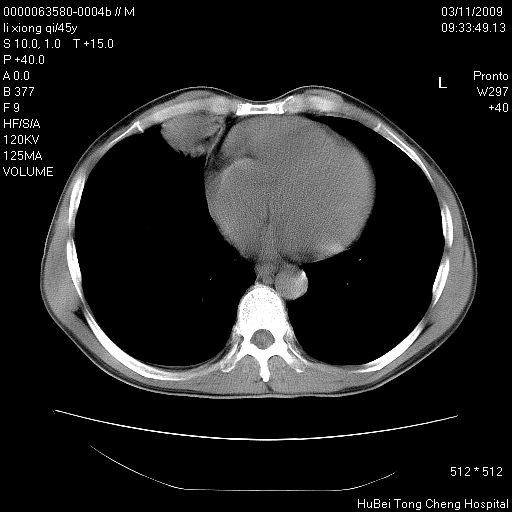

患者 男,45岁。胸痛,咳嗽伴痰中带血1月余。

临床诊断:肺结核?

胸部ct轴位平扫(层厚10mm,螺距1.5,重建间隔10mm),图像如下:

考虑肝癌肺转移